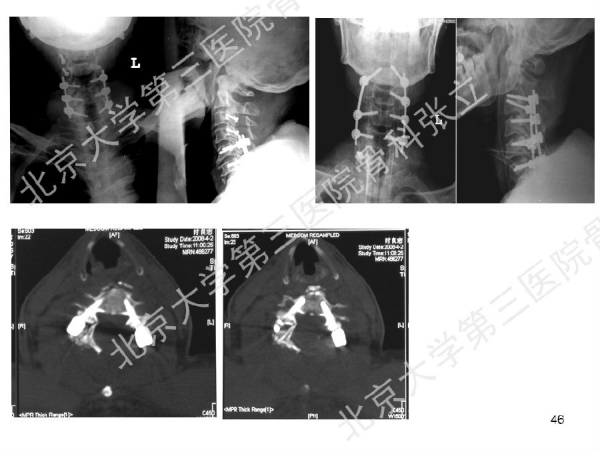

徒手置钉的下颈椎椎弓根钉技术对于很多骨科同道来说,无疑是难度超高、不敢触及的一项技术。已熟练掌握这一技术的北京大学第三医院骨科张立主任医师认为,下颈椎椎弓根钉徒手置钉技术固定可靠,能满足绝大多数后路固定所需,可应用于脊柱外伤、脊柱畸形、脊柱肿瘤,以及CSM伴退变性颈椎后凸畸形。它的优势是:螺钉尾部靠外,不影响椎板成形术;先置钉固定,后开门,更安全;和椎板成形术完美结合,减压、复位、固定一次完成;极少出现脊髓、神经根及椎动脉损伤。